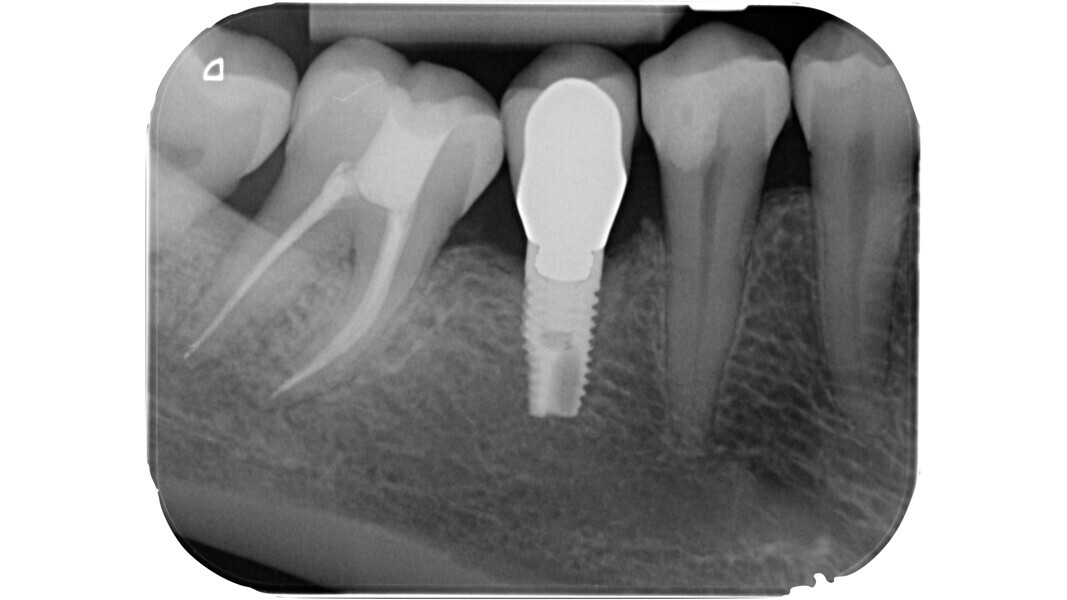

L’étape suivante est la phase de localisation et celle-ci peut s’avérer très difficile, surtout dans les dents calcifiées. Dans ce cas, le praticien doit laisser de côté les instruments rotatifs diamantés et recourir à divers dispositifs spéciaux.

Parfois, il est possible d’élargir davantage la cavité d’accès pour simplifier le sondage et la mise en forme, ce que l’on appelle la phase de finition. Généralement, cette phase est réalisée au moyen d’une fraise Batt (fraise conique à bout rond, non tranchant), mais il est aussi possible de se servir d’inserts soniques ou ultrasoniques spéciaux. Ces dispositifs sont utilisés pour éliminer les surplombs de dentine et obtenir un accès plus rectiligne aux canaux.Leur pointe non tranchante protège le plancher de la cavité pulpaire, tandis que leur forme conique évite la formation de contre-dépouilles